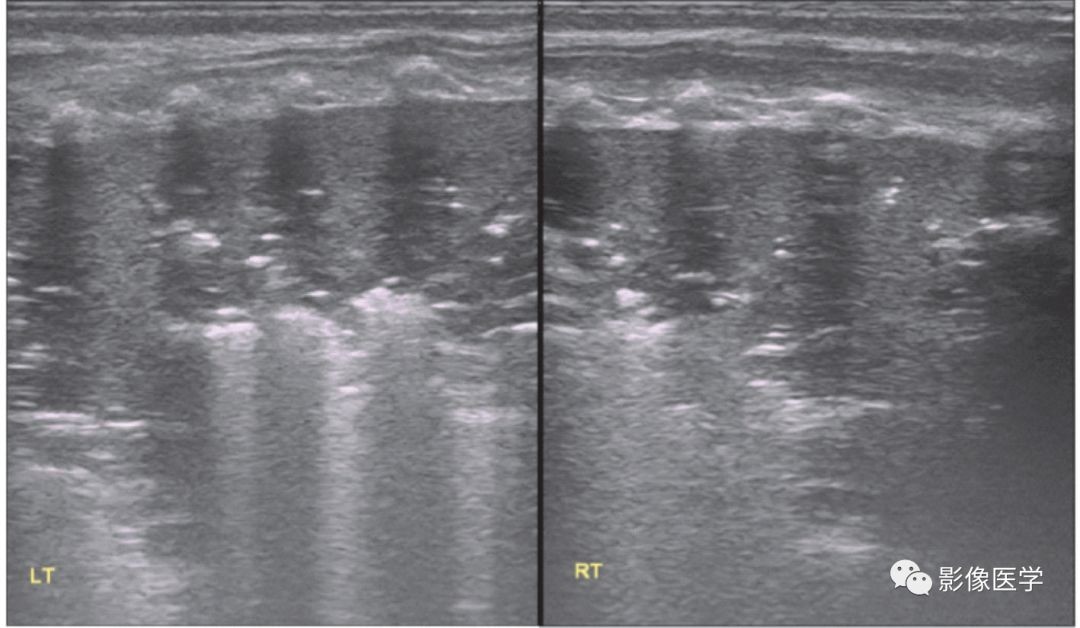

图 6-2 重症感染性肺炎(1)

胎龄38+2周,剖宫产分娩,出生体重3 420g。因呼吸困难3d于出生后20d入院。体温38℃,双肺可闻及密集细湿啰音。血常规:WBC 22×109/L,N 78%,单核细胞比例12.2%,CRP 66.8mg/L。胸部X线检查结果符合新生儿肺炎改变。肺脏超声显示双肺边缘不规则的大面积实变区伴支气管充气征,胸膜线模糊或消失,A线消失。